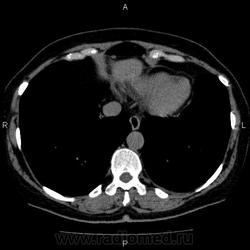

- https://radiomed.ru/sites/default/files/styles/case_slider_image/public/user/5278/10002_0.jpg?itok=S-d8_IwS

Это кальцификация. Бывшая гематома, бывший воспалительный процесс, паразитарное поражение, гемангиома, сосудистая мальформация, злокачественное нечто либо метастаз. Без клиники, пола, возраста и болюсного КТ... ну допустим, я поставлю на солитарный метастаз. И это 50/50, т.е. либо я права, либо нет.

гидативную нежизнеспособную кисту. Гемангиома гиподенсна относительно здоровой паренхимы, да и гематома так выглядеть не может.

На эхинококковую кисту похожа

Похоже на кальцинированную эхинококковую кисту печени; для уточнения КТ с болюсным мультифазным контрастированием; консультации гастроэнтеролога и онколога.

"Образование" 3 года без динамики. На УЗИ написали гемангиому. Спасибо всем.